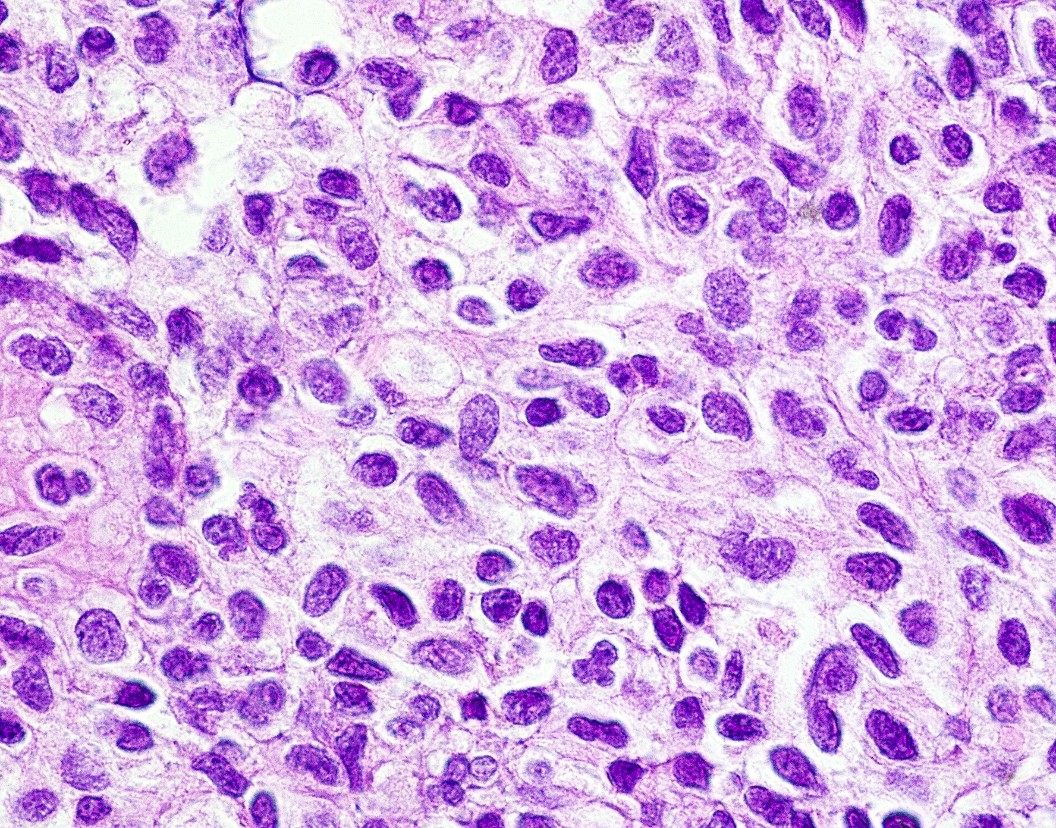

Microscopic (histologic) description

- Well demarcated tumor, often entrapped within skeletal muscle and frequently multilobulated (Am J Surg Pathol 2018;42:1297, Head Neck Pathol 2015;9:315)

- Stromal background may be hyalinized or demonstrate mucoid, myxoid or chondromyxoid areas

- Cords, strands or sheets of oval, round, fusiform or polygonal bland cells, sometimes arranged in a reticular / net-like or globoid pattern (Am J Surg Pathol 2018;42:1297)

- Myxoglobulosis-like changes have been noted (Virchows Arch 2003;442:302)

- May focally demonstrate fine calcifications, cellular atypia, necrosis, multinucleated giant cells (Am J Surg Pathol 2018;42:1297, Head Neck Pathol 2015;9:315, Oral Surg Oral Med Oral Pathol Oral Radiol Endod 1996;82:417)

- Cystic, slit-like spaces or hemorrhagic areas often noted (Head Neck Pathol 2014;8:329)

- Mitotic figures not seen (Head Neck Pathol 2015;9:315)

Microscopic (histologic) images